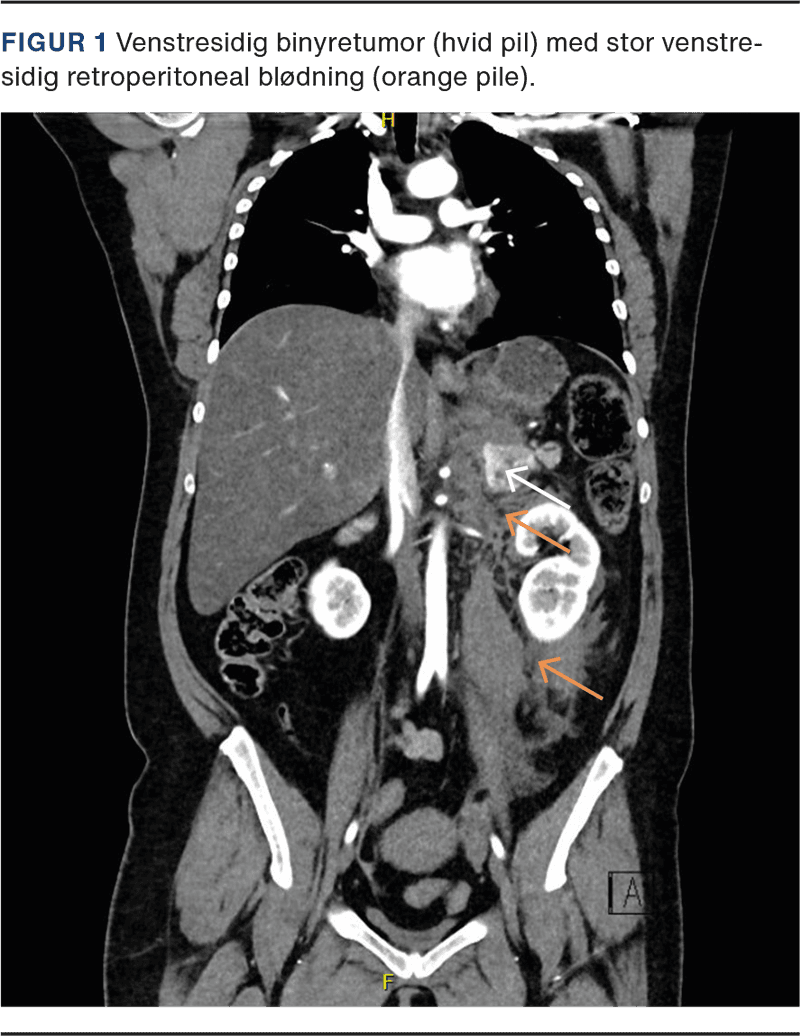

To år senere blev hun indlagt med COVID-19-infektion og pludselig stigning i blodtrykket til 223/120 mmHg ledsaget af hovedpine. Den antihypertensive behandling blev suppleret med labetalol, og hun blev henvist til et kardiologisk ambulatorium, hvor man noterede, at hun var familiært disponeret til hypertension. Hun var nu i antihypertensiv behandling med spironolacton, bendroflumethiazid, nifedipin, losartan og labetalol. Ved opfølgende besøg anførtes det, at patienten flere gange havde haft palpitationer og ubehag i brystet og maven. Der blev ordineret måling af plasmametanefriner. Kort tid efter blev patienten indlagt akut med brystsmerter, et blodtryk på 216/149 mmHg og en puls på 143 slag/min. Hun fremtrådte utilpas, bleg og klamtsvedende med ømhed i venstre side af maven. De biokemiske analyser viste kraftig leukocytose uden CRP-stigning og forhøjet kreatinin. Der blev bestilt akut CT af thorax og abdomen på mistanke om aortadissektion. Her blev der fundet venstresidig binyreblødning (Figur 1) formodentlig udgående fra en binyretumor. Patienten blev overflyttet til Rigshospitalet mhp. akut embolisering. Ved ankomsten var blodtrykket faldet til 88/62 mmHg, og en A-gasanalyse viste et fald i hæmoglobinniveauet fra 8,1 til 7,2 mmol/l. Hun blev akut emboliseret i både aa. suprarenales media og superior.